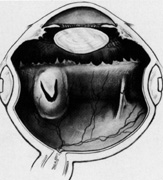

After the subretinal space is entered, the needle is quickly removed and the site inspected under magnification. Usually the presence of fluid around the needle signifies entry into the subretinal space (Fig. 30). As the fluid drains, it is important to maintain a relatively normal and constant intraocular pressure to prevent retinal incarceration or hemorrhage. Indentation of globe at the ora serrata in the meridian of the drainage site facilitates elevation of the retina over the site and allows movement of subretinal fluid to the drainage site (Fig. 31). As the fluid drains, the loss of intraocular volume can be compensated for by indentation with cotton-tipped applicators starting 180° away from the drainage site. The site itself is not manipulated so long as good drainage of subretinal fluid proceeds.

Fig. 30. Entry into subretinal space avoiding any obvious choroidal vessels.